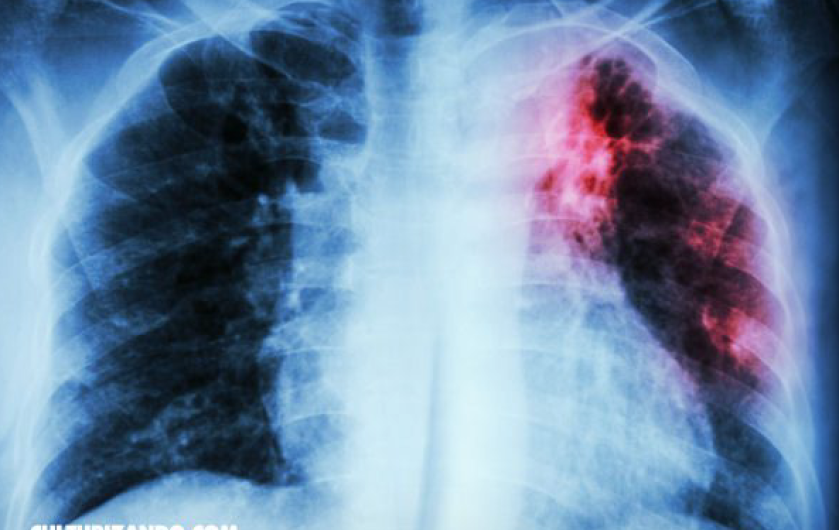

En lo que va del año, se han registrado un total de 48 casos nuevos de personas portadoras de Tuberculosis, de acuerdo con el departamento de Microbacteriosis de la Jurisdicción Sanitaria 5.

La información fue dada a conocer por el encargado del departamento, el doctor Oscar González Arrambide, quien indicó que en comparación con el año pasado, se atendían 234 casos, solo que alrededor de 160 pacientes terminaron su tratamiento.

De acuerdo con Gonzales Arrambide 17 casos pertenecen a la Secretaría de Salud, 20 a la unidad de Medicina Familiar (UMF) No. 78, son 8 de la UMF No. 76 del ISSSTE.

“Hemos tenido un poco de incremento, esto lo hemos visto reflejado por los migrantes que han regresado, nos han estado reportando pacientes que vienen con tratamiento, diagnosticados y aquí les damos seguimiento.” dijo.

“En cuanto a menores de edad afectados por Tuberculosis oscilan entre los 15 y 19 años de edad, más un niño de 5 años que está a través del tratamiento binacional, las personas que tengan más de quince días con tos y flemas, deben realizarse el examen para descartar si es tuberculosis” indicó González Arrambide.